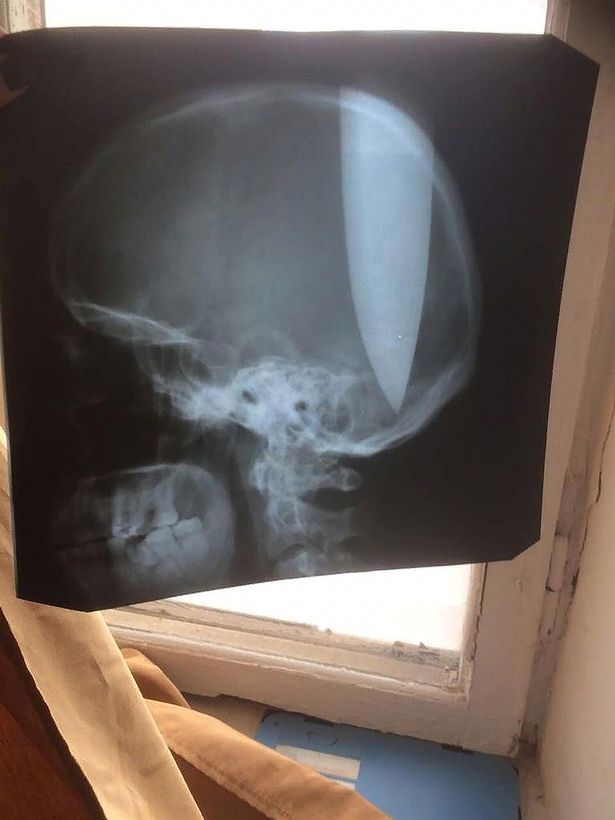

Các bác sĩ lập tức chụp X-quang sau khi Zhokhov được đưa tới bệnh viện. Họ phải thốt lên ngạc nhiên khi não của người đàn ông này không bị tổn thương và ông ta vẫn giữ được mạng sống.

Ảnh chụp X-quang cho thấy lưỡi dao nằm giữa hai thùy não. Ảnh: east2west news

Lưỡi dao được các bác sĩ phẫu thuật gắp bỏ. Họ cho biết, sau phẫu thuật, bệnh nhân vẫn sống nhưng trong tình trạng “nghiêm trọng” vì nguy cơ nhiễm trùng cao.

“Thật khủng khiếp. Ngay cả những y tá dạn dày kinh nghiệm, những người thấy nhiều cảnh này, mà cũng không thể chịu nổi. Kết quả chụp X-quang cho thấy lưỡi dao xuyên giữa hai bán cầu não. Các bác sĩ địa phương cũng không dám kéo con dao khỏi đầu. Họ yêu cầu bệnh viện khu vực cử các chuyên gia đến giúp đỡ”, một phát ngôn viên của bộ Khẩn cấp Nga cho biết.